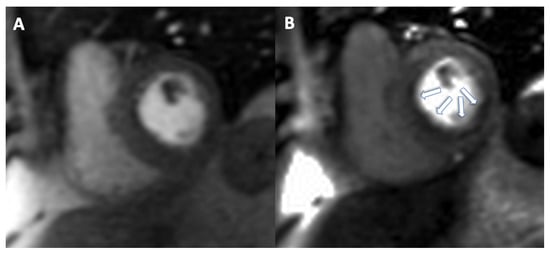

Stress imaging with nuclear medicine is widely

available in clinical practice, allowing the evaluation of myocardial ischemia.

Although stress CTP, myocardial SPECT and myocardial PET require the use of

ionizing radiation, it is important to consider that with CTP it is possible to

evaluate CAD beyond myocardial ischemia. Compared to SE and stress CMR, using

nuclear medicine it is possible to evaluate ischemic myocardium, however it is

mandatory to consider the use of radiation. A representative case is shown in Figure 8.

Figure 8.

(Panel (A)) dynamic myocardial 13N-ammonia PET/CT in a normal patient. First row shows representative left ventricular perfusion myocardial slices under maximal vasodilator stress (with quantitative myocardial stress flow values); second row shows representative left ventricular perfusion myocardial slices at rest (with quantitative myocardial rest flow values). Absolute flow values are presented in the table and flow reserve is automatically calculated for the different territories and also for the whole left ventricle (global). (Panel (B)) myocardial 13N-ammonia PET/CT stress/rest perfusion study in the same patient. The distribution of perfusion is homogeneous both at stress and at rest.